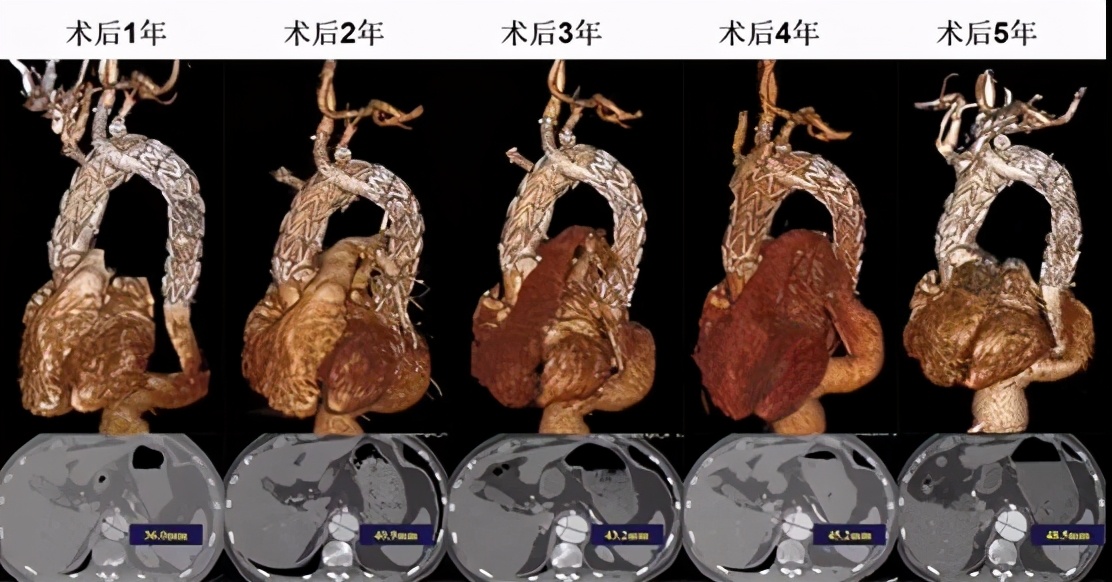

术后:全腔内&平行支架技术是否适用于马凡综合征患者的主动脉弓部病变,目前远期效果仍存疑。术后5年随访显示弓部形态良好,远端胸降主动脉&腹主动脉存在扩张趋势。

后期问题

对于这类马凡综合征患者,近端开放/腔内修复术后,术后远端残余夹层率65.2%~77.8%。术后患者主动脉直径及长度逐年增加,原发夹层部位主动脉增速加剧(1~7 mm/年)。10年内再次手术干预率为15%~35.5%。所以,对于这类患者后期,处理好弓部之后,还需要密切关注远端是否发生瘤样扩张,一旦发生积极干预。目前,新的技术还可实现从弓部到胸主动脉远端一体修复(全腔内主动脉修复一体化支架植入)。